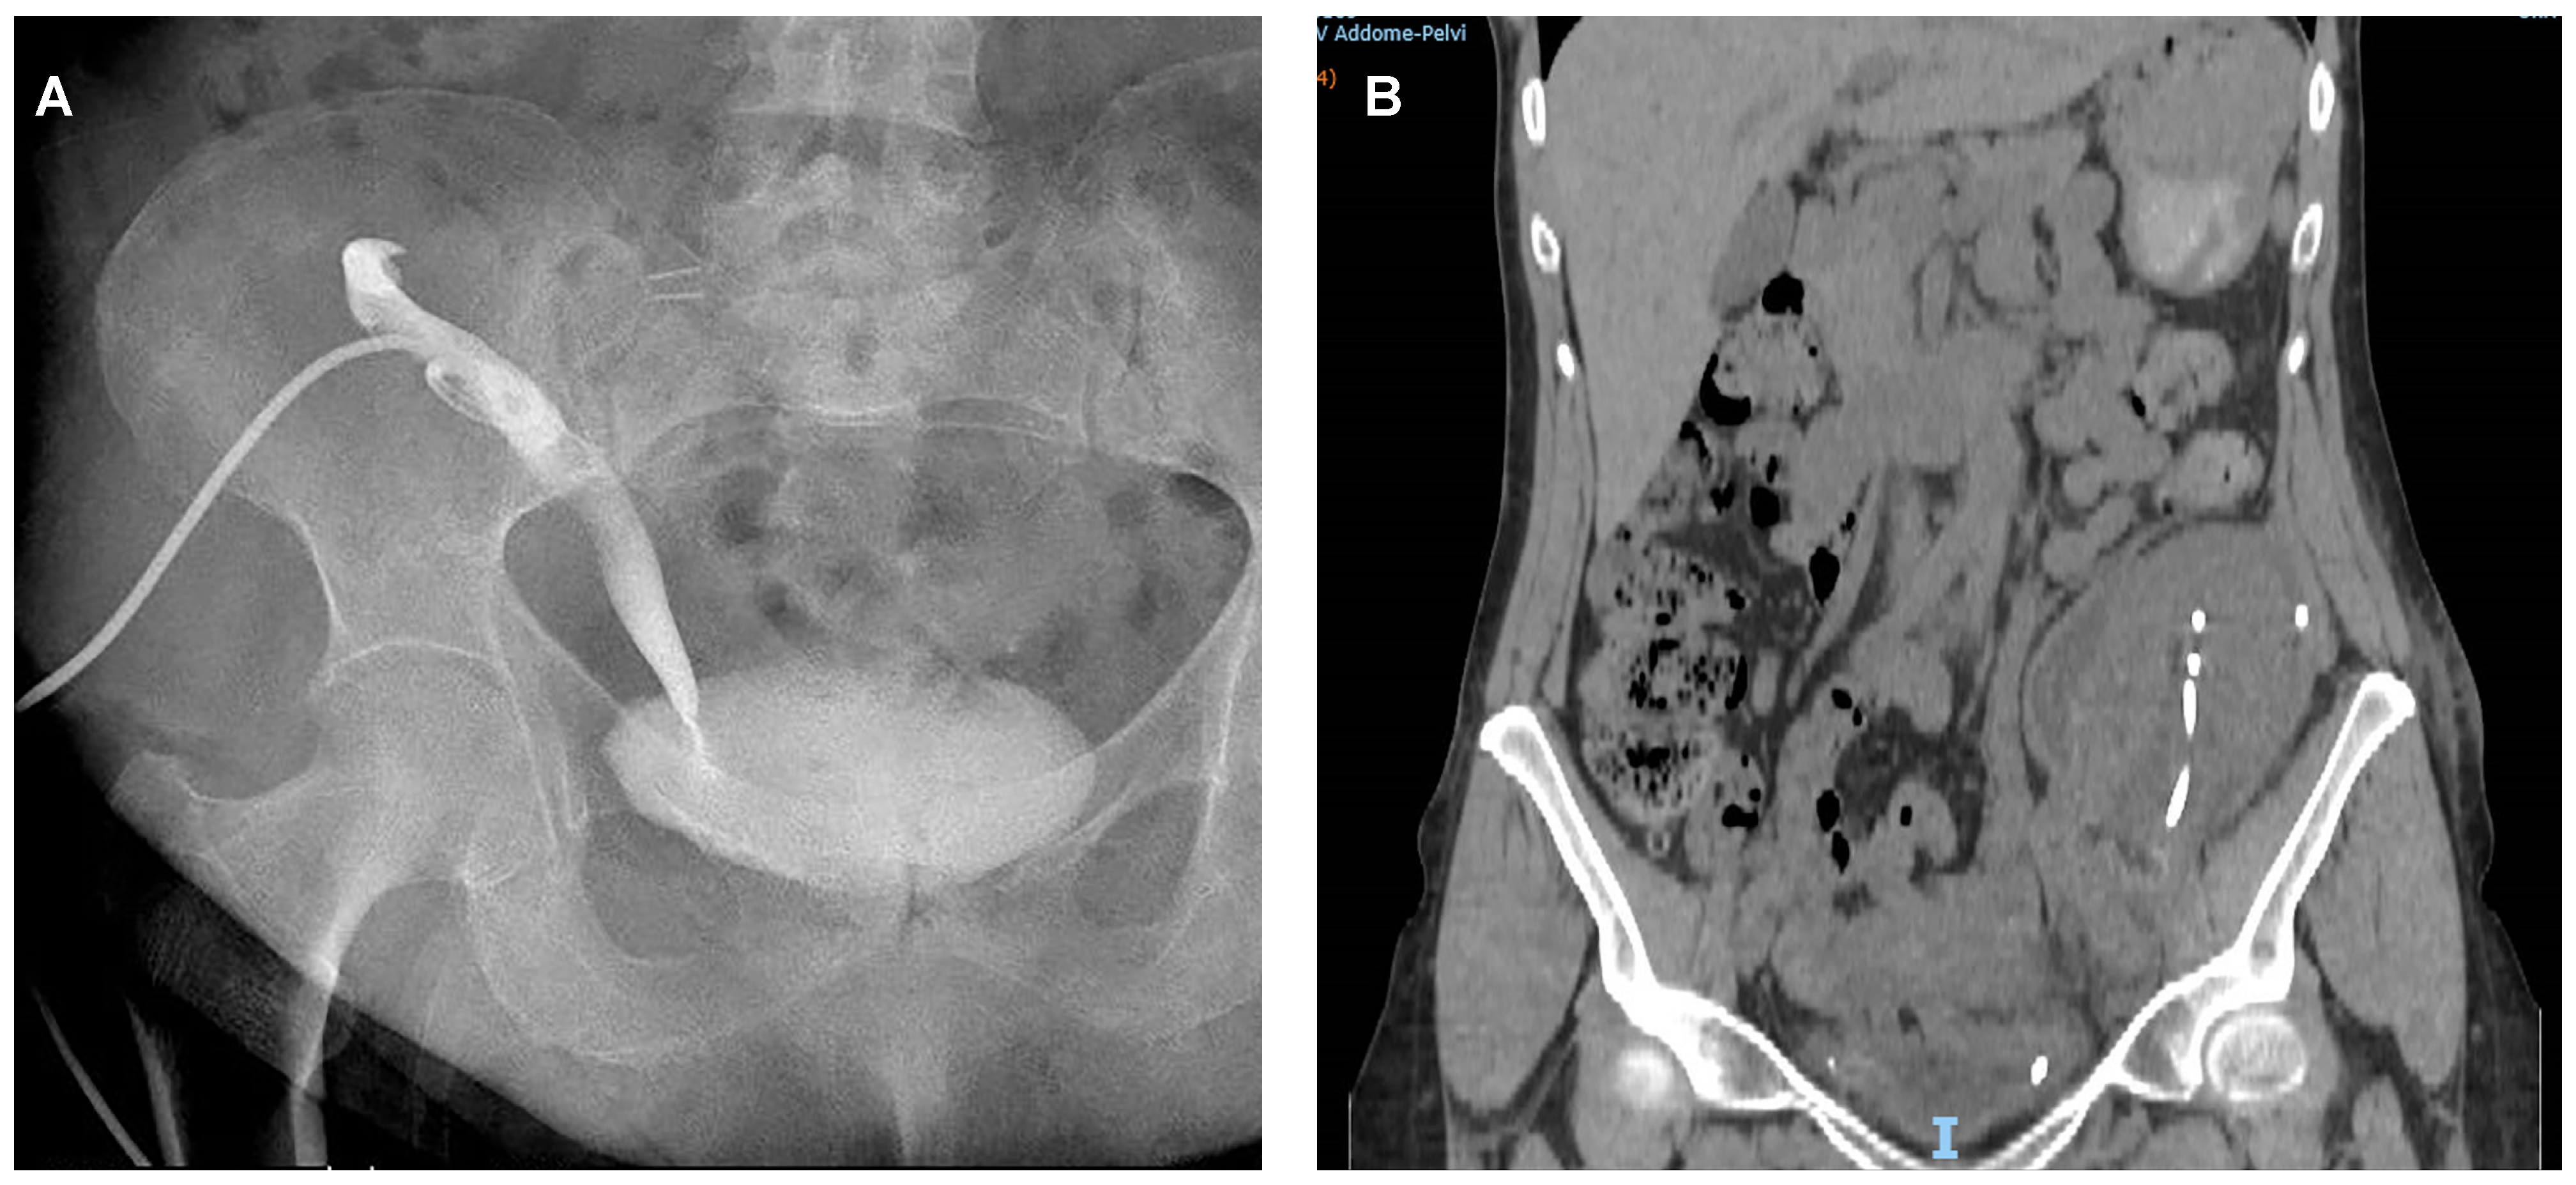

| Type of UC treatment: | |

| ● Nephrostomy + ureteral stenting | 17 (53.1%) |

| ● Cystoscopy + ureteral stenting | 3 (9.4%) |

| ● Nephrostomy | 2 (6.2%) |

| ● Foley catheter insertion | 5 (15.6%) |

| ● Surgical intervention | 5 (15.6%) |